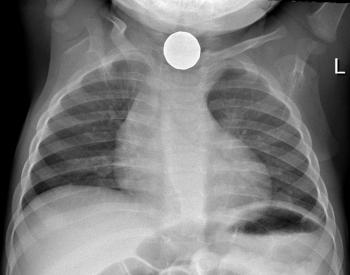

La composición del objeto estará relacionada con la capacidad de producir daño por el contacto del mismo con las paredes del tubo digestivo. Esto es especialmente importante cuando el objeto se detiene en un sector sin avanzar. Las pilas botón constituyen un ejemplo característico pudiendo producir en su trayecto quemaduras eléctricas de bajo voltaje y necrosis de la mucosa digestiva por liberación de su contenido tóxico (mercurio, zinc, óxido de plata, litio y, a veces, hidróxido sódico o potásico).